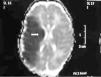

Se realizaron EEG y ecografía cerebral a las 24 h de vida que fueron normales. Ante la persistencia de la hipotonía, se realizó al quinto día de vida RM cerebral que mostró hallazgos compatibles con una lesión isquémica en el territorio arterial de la cerebral media bilateral, asociado a hemorragias subcorticales en dicho territorio, así como a nivel de sustancia blanca periauricular izquierda (fig. 3).

Figura 3.T1 coronal. Zona de infarto en fase hemorrágica en sustancia blanca paraventricular izquierda dependiente del territorio de la ACM izquierda. Áreas hemorrágicas corticosubcorticales del mismo hemisferio.